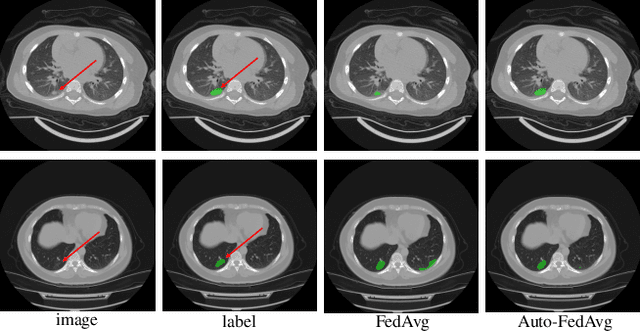

Abstract:Federated learning (FL) enables collaborative model training while preserving each participant's privacy, which is particularly beneficial to the medical field. FedAvg is a standard algorithm that uses fixed weights, often originating from the dataset sizes at each client, to aggregate the distributed learned models on a server during the FL process. However, non-identical data distribution across clients, known as the non-i.i.d problem in FL, could make this assumption for setting fixed aggregation weights sub-optimal. In this work, we design a new data-driven approach, namely Auto-FedAvg, where aggregation weights are dynamically adjusted, depending on data distributions across data silos and the current training progress of the models. We disentangle the parameter set into two parts, local model parameters and global aggregation parameters, and update them iteratively with a communication-efficient algorithm. We first show the validity of our approach by outperforming state-of-the-art FL methods for image recognition on a heterogeneous data split of CIFAR-10. Furthermore, we demonstrate our algorithm's effectiveness on two multi-institutional medical image analysis tasks, i.e., COVID-19 lesion segmentation in chest CT and pancreas segmentation in abdominal CT.

Abstract:The recent outbreak of COVID-19 has led to urgent needs for reliable diagnosis and management of SARS-CoV-2 infection. As a complimentary tool, chest CT has been shown to be able to reveal visual patterns characteristic for COVID-19, which has definite value at several stages during the disease course. To facilitate CT analysis, recent efforts have focused on computer-aided characterization and diagnosis, which has shown promising results. However, domain shift of data across clinical data centers poses a serious challenge when deploying learning-based models. In this work, we attempt to find a solution for this challenge via federated and semi-supervised learning. A multi-national database consisting of 1704 scans from three countries is adopted to study the performance gap, when training a model with one dataset and applying it to another. Expert radiologists manually delineated 945 scans for COVID-19 findings. In handling the variability in both the data and annotations, a novel federated semi-supervised learning technique is proposed to fully utilize all available data (with or without annotations). Federated learning avoids the need for sensitive data-sharing, which makes it favorable for institutions and nations with strict regulatory policy on data privacy. Moreover, semi-supervision potentially reduces the annotation burden under a distributed setting. The proposed framework is shown to be effective compared to fully supervised scenarios with conventional data sharing instead of model weight sharing.